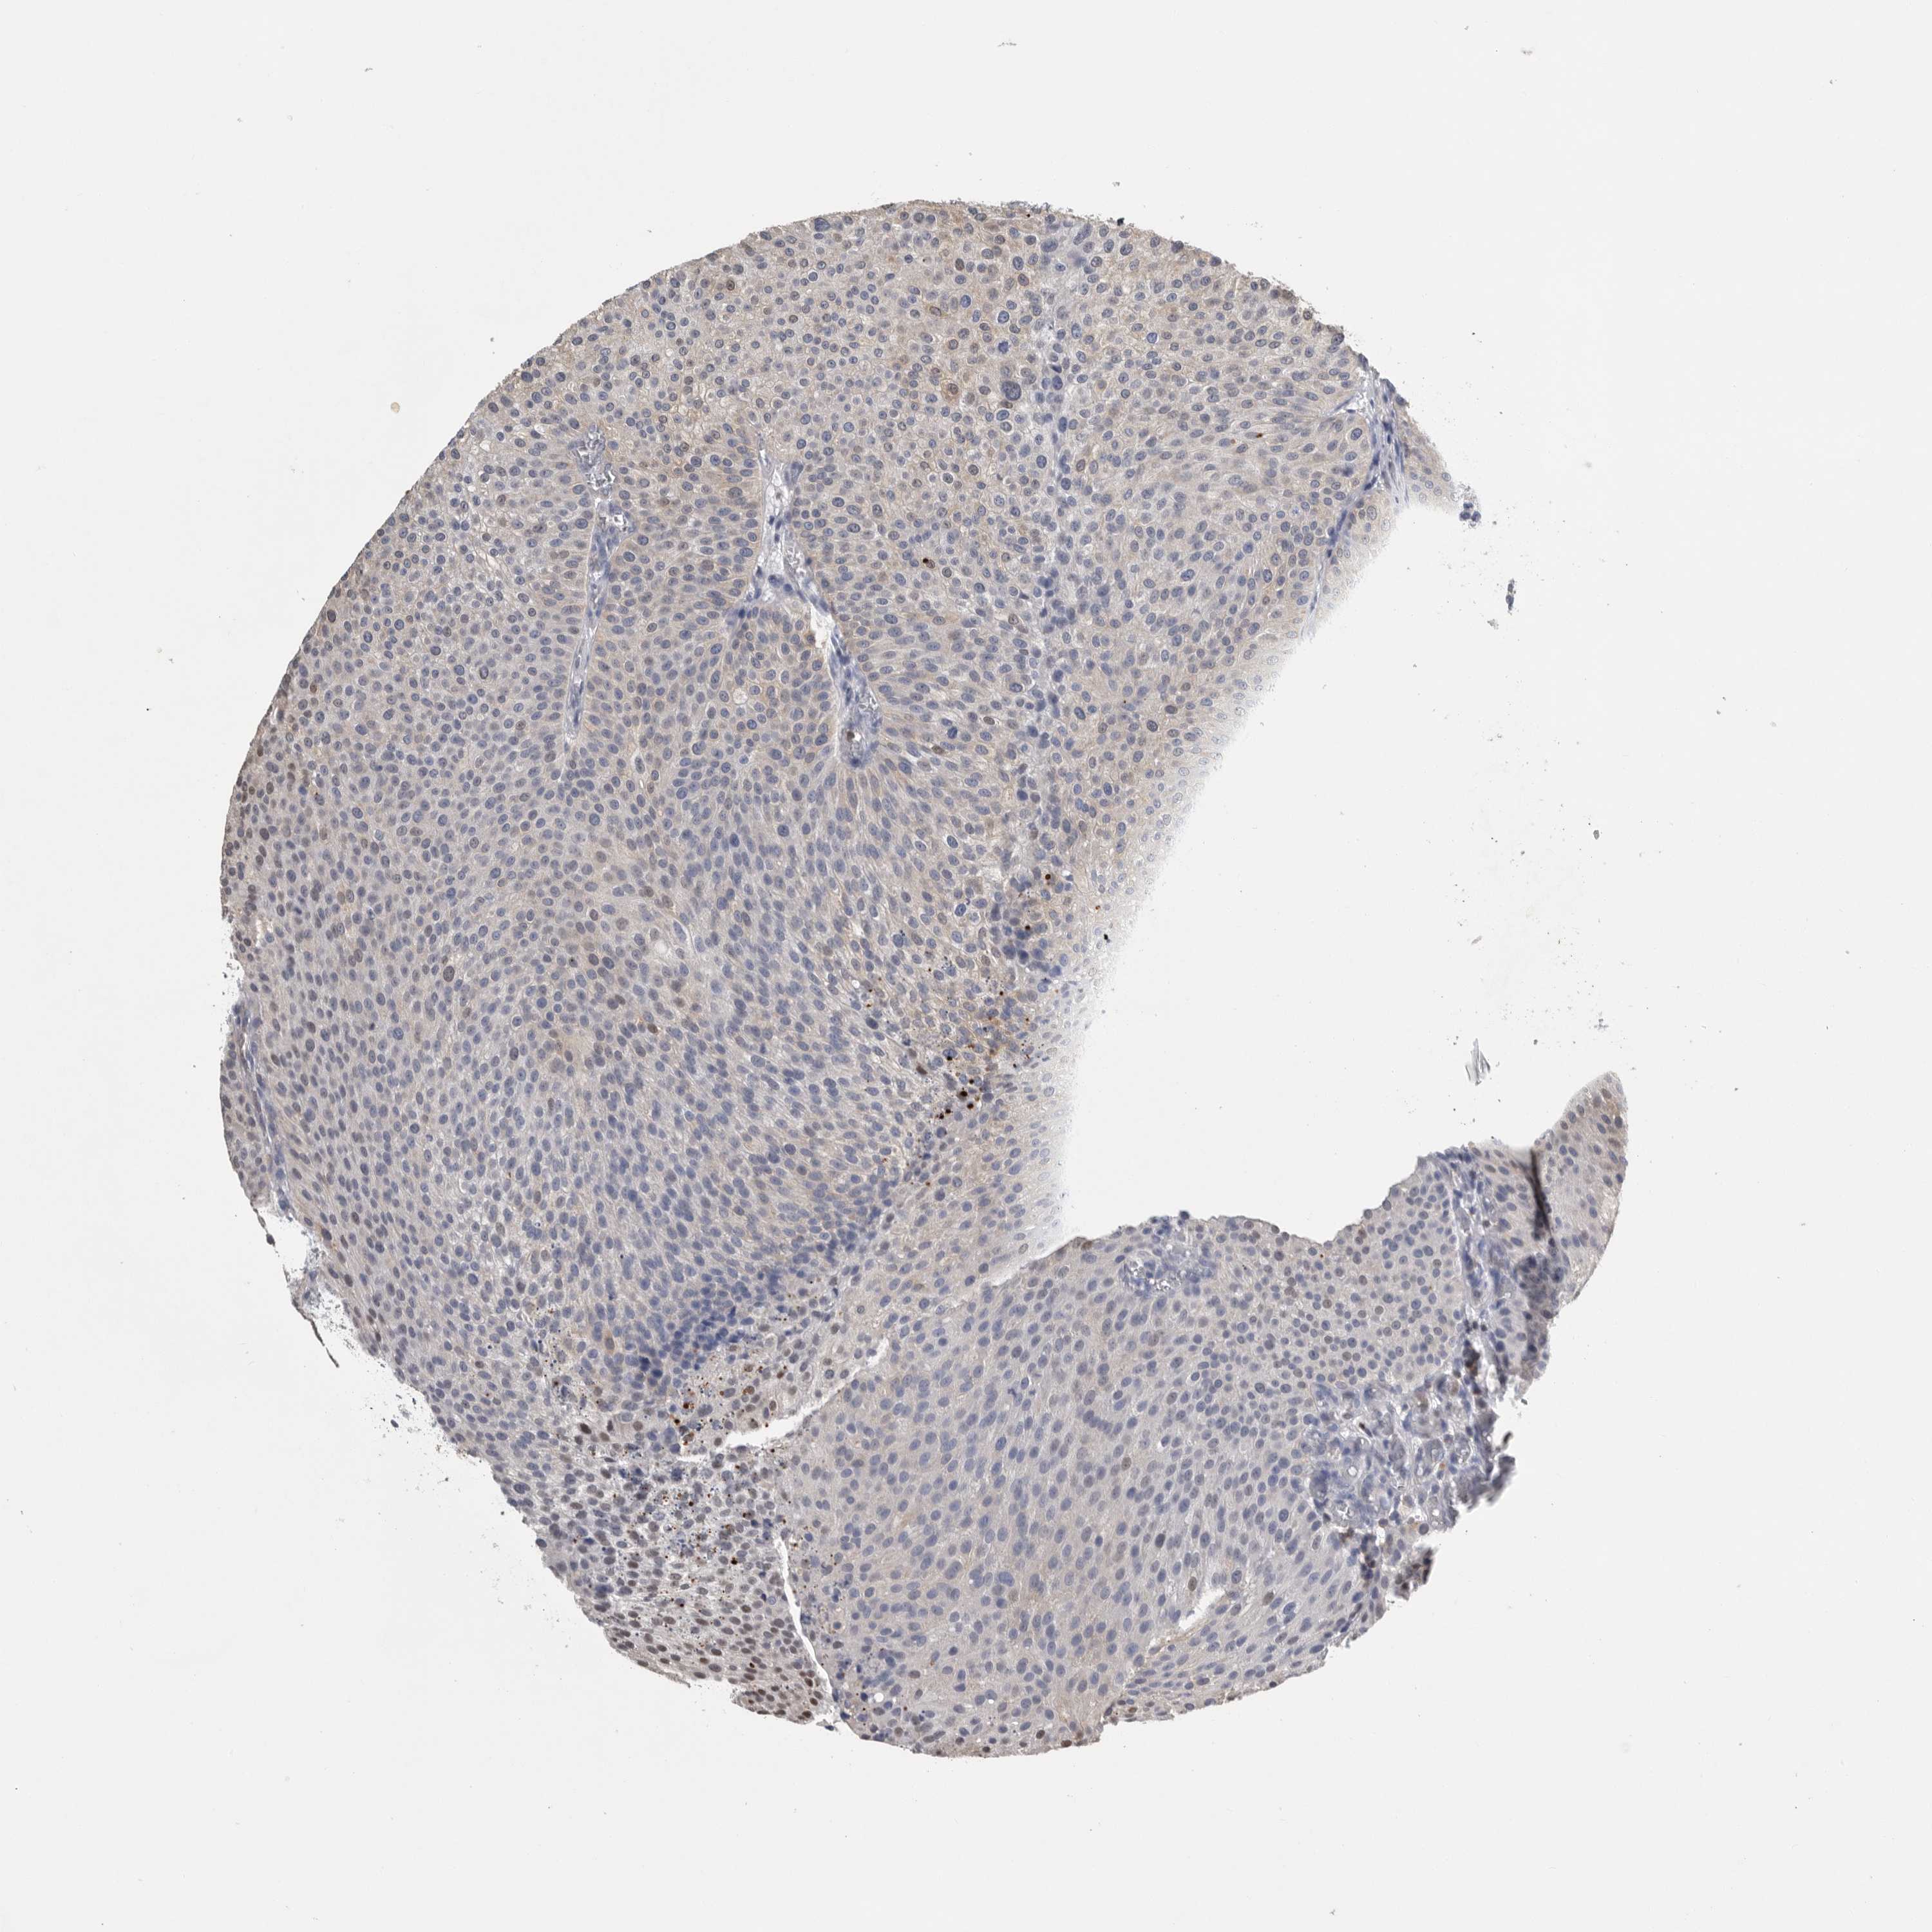

UROTHELIAL CANCER - Protein expressioni

A mouse-over function shows sample information and annotation data. Click on an image to view it in a full screen mode. Samples can be filtered based on level of antibody staining by selecting one or several of the following categories: high, medium, low and not detected. The assay and annotation is described here.

Note that samples used for immunohistochemistry by the Human Protein Atlas do not correspond to samples in the TCGA dataset.

Antibody stainingi

Antibody staining in the annotated cell types in the current human tissue is reported as not detected, low, medium, or high, based on conventional immunohistochemistry profiling in selected tissues. This score is based on the combination of the staining intensity and fraction of stained cells.

Each image is clickable and will lead to virtual microscopy that enables deeper exploration of all samples and also displays staining intensity scores, fraction scores and subcellular localization as well as patient and tissue information for each sample.

Antibody HPA001032

Antibody HPA027214

Antibody CAB037024

Urothelial carcinoma, High grade

Urothelial carcinoma, Low grade

Urothelial carcinoma, NOS